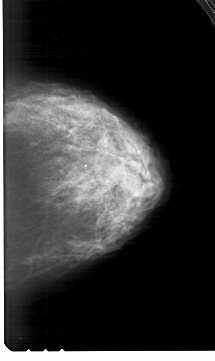

A_1983_1.RIGHT_MLO

RIGHT_MLO LINES 6256 PIXELS_PER_LINE 3796 BITS_PER_PIXEL 12 RESOLUTION 43.5 NON_OVERLAY